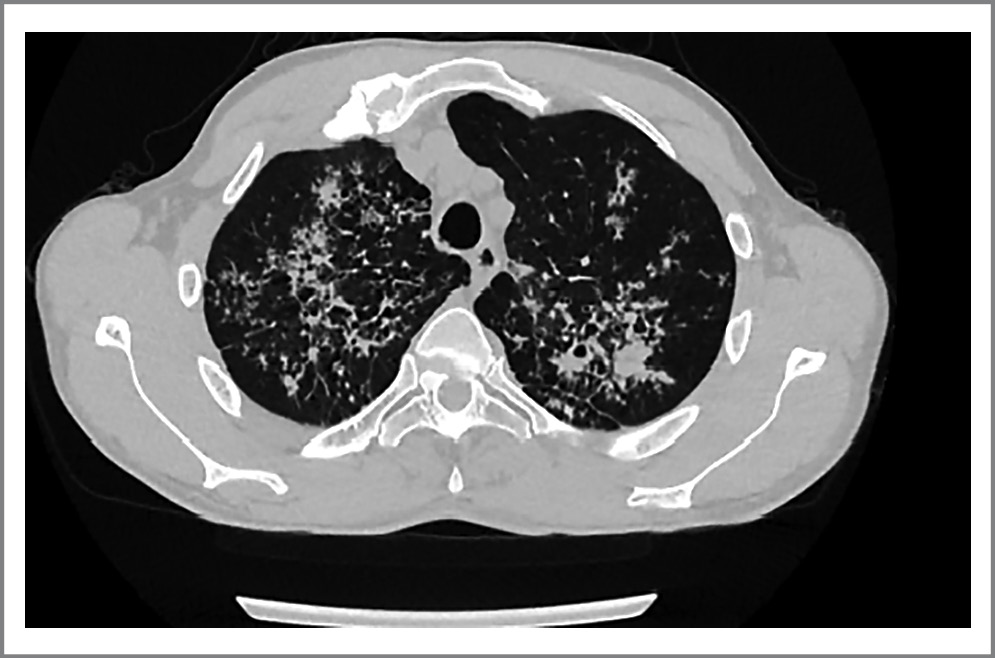

- Пациентка О. 69 лет, с 2017 г. наблюдается в ГБУЗ «МКНЦ имени А.С. Логинова» с БК тонкой кишки. В связи с неэффективностью азатиоприна с апреля 2020 г. инициирована терапия препаратом цертолизумаба пэгол. Предварительно исключена ТИ по данным РГ ОГК и ДСТ. После первого введения цертолизумаба пэгол развилась нежелательная реакция в виде удушья и тахикардии. Препарат отменен. Спустя 4 мес начата терапия ведолизумабом с положительным эффектом. В мае 2021 г. у больной повысилась температура тела до 40°С. По данным КТ ОГК в легких выявлены очаги с деструкцией, левосторонний плеврит, в мокроте обнаружены КУМ (рис. 4).

Рис. 4. КТ ОГК: очаговые изменения легких с деструкцией у пациентки О.

Fig. 4. CT scan of the thoracic organs: focal changes of the lungs with destruction in the patient O.

Установлен диссеминированный ТБ легких в фазе инфильтрации и распада. Назначена противотуберкулезная терапия (этамбутол, пиразинамид, изониазид, 61 доза). Ведолизумаб отменен. В последующем пациентка продолжила лечение месалазином 4 г/сут, ремиссия БК сохраняется по настоящее время.